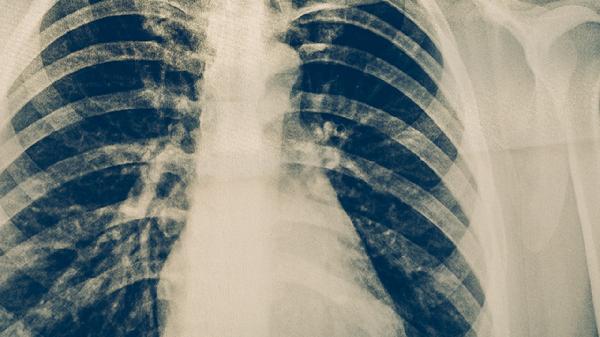

对于体积大于3厘米的肺良性肿瘤,建议每6-12个月进行CT随访。生长速度突然加快、边缘毛刺征或出现胸膜牵拉等影像学改变时,需警惕性质变化。